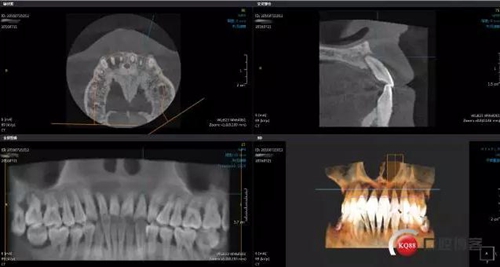

術(shù)前左上2 CBCT

術(shù)前右上2 CBCT